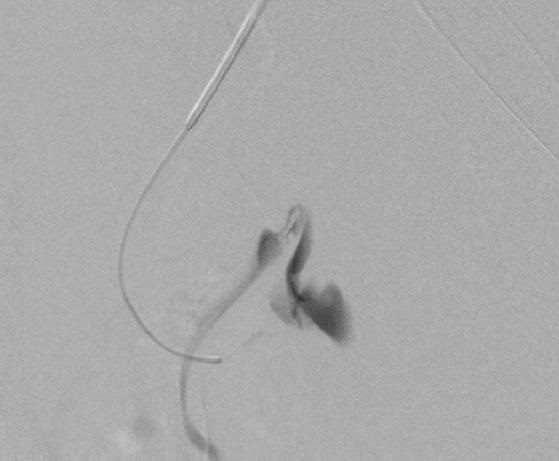

外伤后出血的栓塞

外伤后可见造影剂外溢 |

微导管选择至出血血管 |

出血血管的微弹簧栓子栓塞 |

栓塞后造影 |